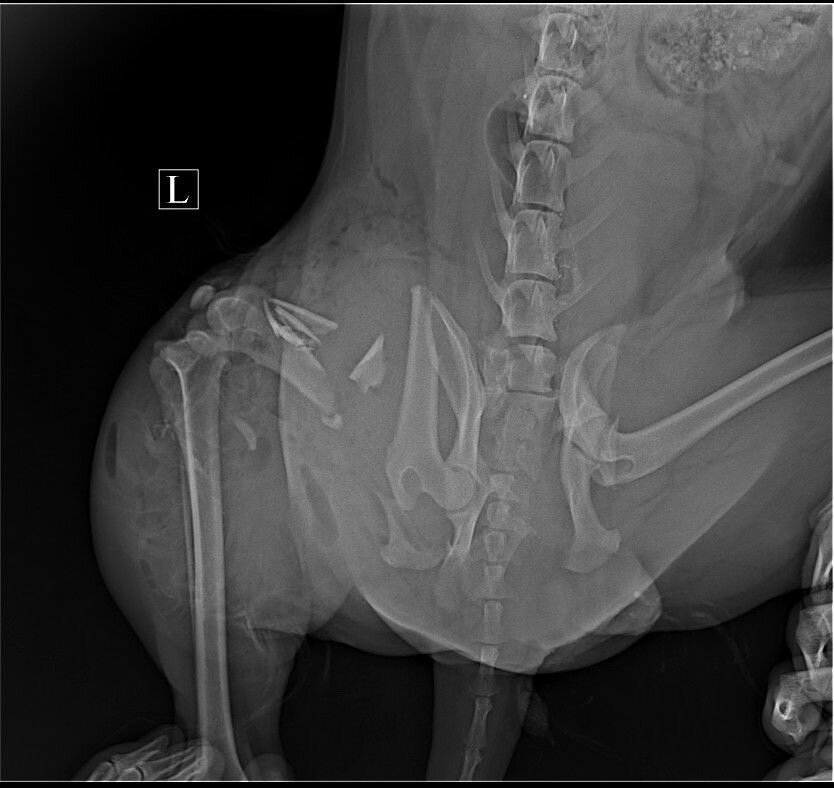

Очень ВАЖНЫЙ СБОР, для сбитой собачки! Диагноз у Дафни: оскольчатый перелом подвздошной кости (с права) и ПЕРЕЛОМ ТАЗА. За такую сложную операцию никто особо из тех докторов, кто вызывает у нас доверие-не брался. А Спартак Анатольевич (Биота) был не в городе, пришлось ждать. В итоге срочно прооперировали собачку, помните, собирали с вами денежки на оплату операции, когда Дафни была уже на операционном столе. Божечки, вы нам так помогли! Мы оплатили ПЕРВУЮ операцию в клинике!

Но, борьба за НОРМАЛЬНУЮ жизнь на четырех лапках ПРОДОЛЖАЕТСЯ! Теперь нужно собрать такую же сумму 44 000 рублей на вторую операцию. Дафни будут делать остеосинтез, чтобы она смогла ходить! Если не собрать поломанный таз, собачка останется ИНВАЛИДОМ, и ходить уже не сможет никогда... И зачастую, у таких животных, НЕТ шанса найти ДОМ. А приют-это единственное спасение!